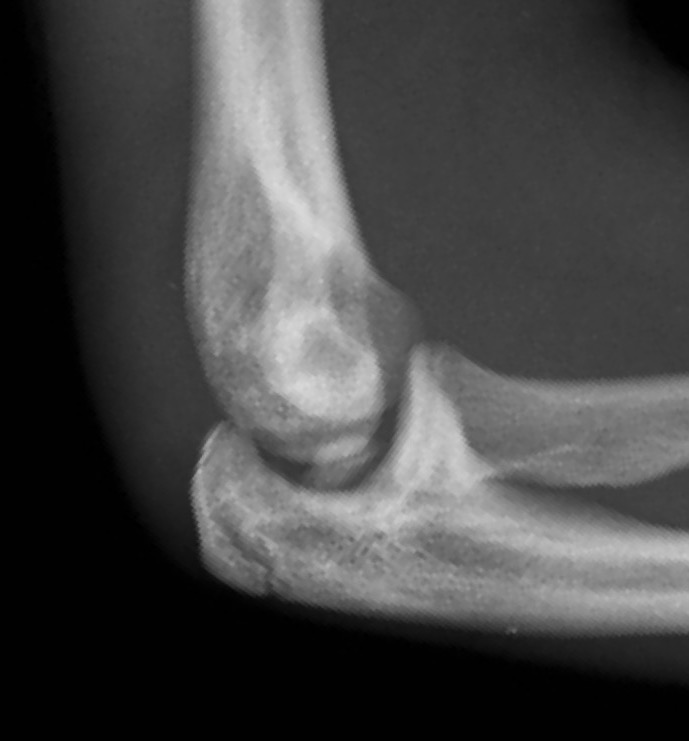

Incarcerated medial epicondyle fracture